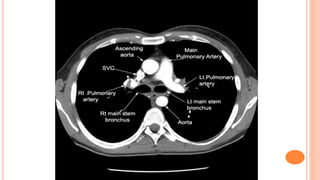

(2) CT

CT at level of Aortic Arch

CT at levelof Aortic Arch